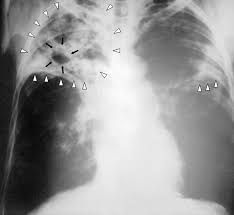

Tuberculosis

Tuberculosis is a bacterial infection that is also known as TB. It can be fatal if not treated. TB most often affects your lungs, but can also affect other organs like your brain.